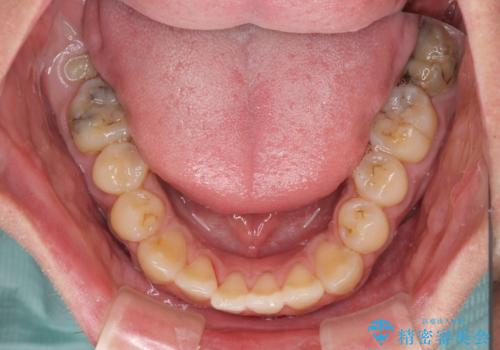

- 前歯のデコボコと上下のクロスバイトを気にして来院された患者様です。

インビザラインを用い、IPR(歯と歯の間を削る)と歯列全体を拡大させることで、歯並びを整えていくこととしました。

上の前歯が下の前歯を乗り越える際、奥歯がほとんど咬めない時期があり、乗り越えた後も、インビザライン特有の奥歯の咬みにくさが続きました。

咬み合わせ改善のために治療期間を要しましたが、最終的に奥歯はしっかりと咬めるようになりました